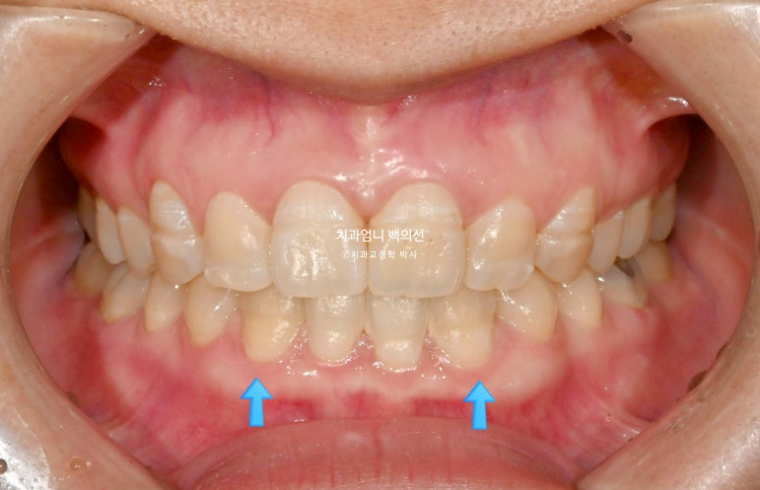

23년 10월 교정치료를 위해 찾아오신 30대 환자분입니다.

23.10

아래 앞니 사이에 벌어진 공간이 있고 위 앞니는 덧니가 있습니다.

앞니에 울퉁불퉁한 띠가 있는데 법랑질저형성증 입니다.

앞니가 튀어나와 돌출도 있습니다.

아래 앞니 4개 중 2개가 없습니다.

태어날때부터 없는 경우를 선천적 결손이라고 합니다.